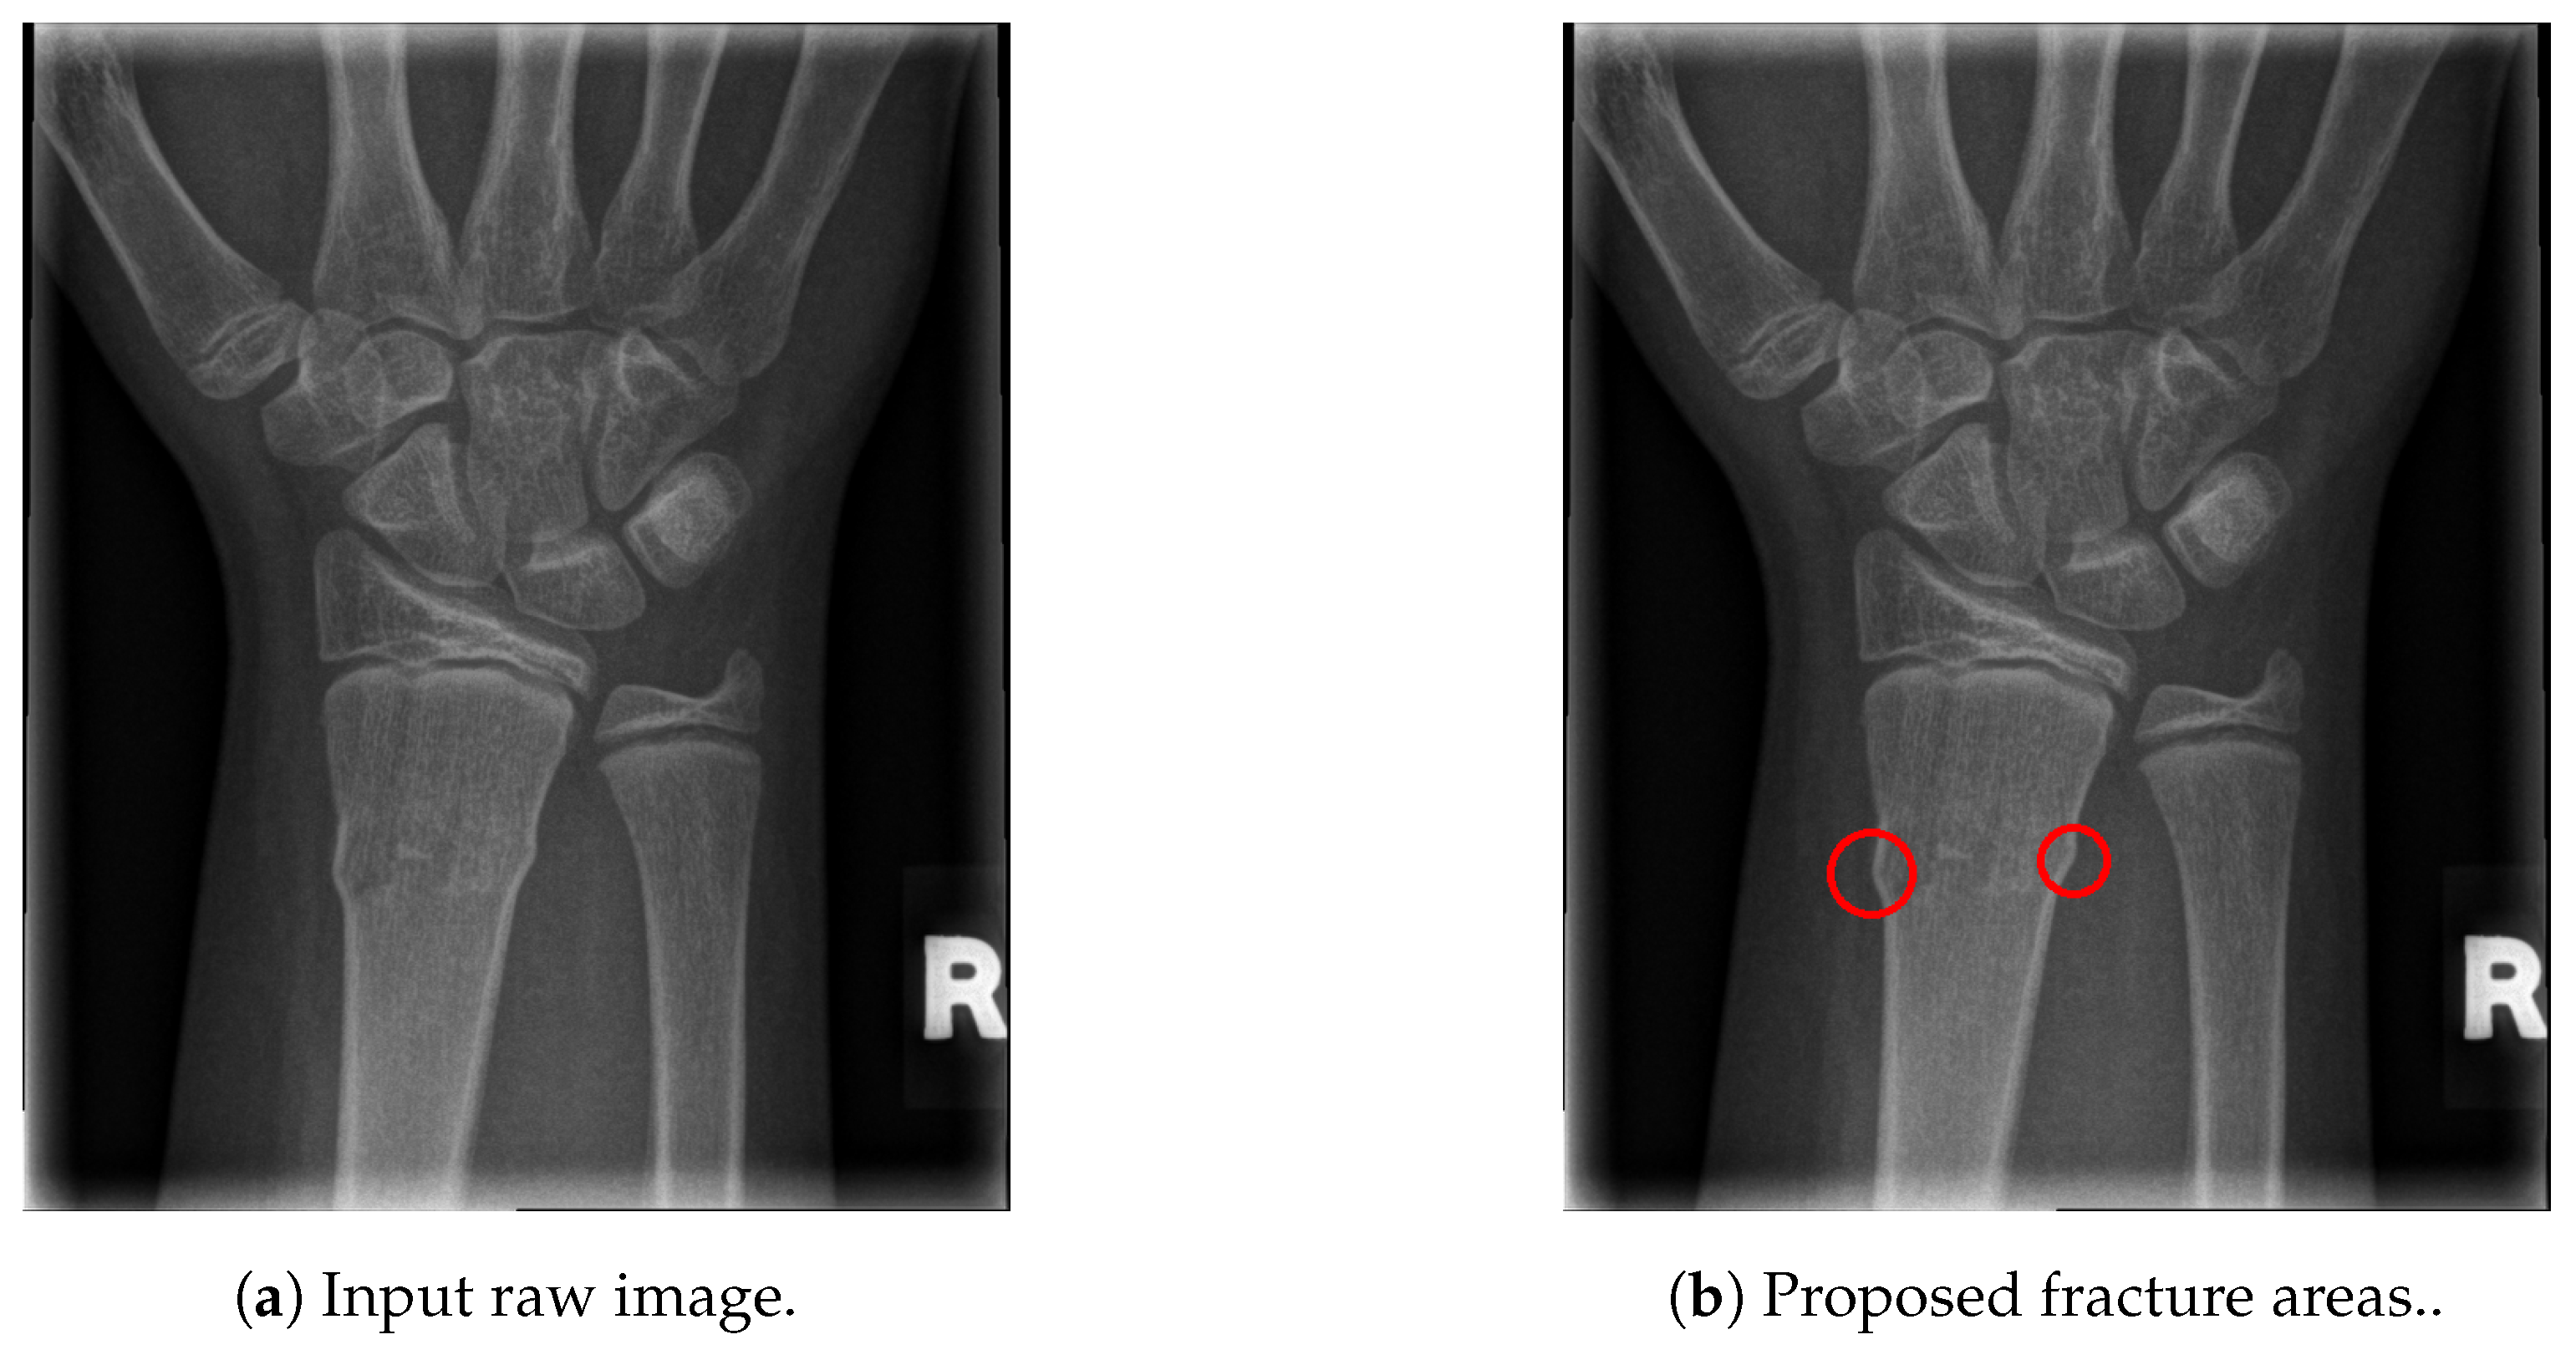

2.5. Fracture Detection